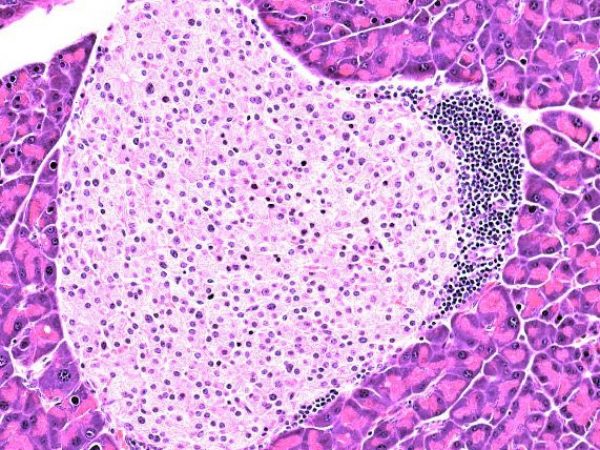

Fatal Attraction, Yaima Luzardo, Clayton E. Mathews, & Molecular Pathology Core